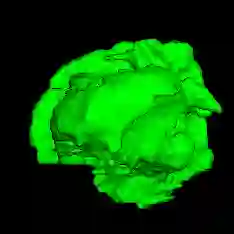

Automatic and accurate tumor segmentation on medical images is in high demand to assist physicians with diagnosis and treatment. However, it is difficult to obtain massive amounts of annotated training data required by the deep-learning models as the manual delineation process is often tedious and expertise required. Although self-supervised learning (SSL) scheme has been widely adopted to address this problem, most SSL methods focus only on global structure information, ignoring the key distinguishing features of tumor regions: local intensity variation and large size distribution. In this paper, we propose Scale-Aware Restoration (SAR), a SSL method for 3D tumor segmentation. Specifically, a novel proxy task, i.e. scale discrimination, is formulated to pre-train the 3D neural network combined with the self-restoration task. Thus, the pre-trained model learns multi-level local representations through multi-scale inputs. Moreover, an adversarial learning module is further introduced to learn modality invariant representations from multiple unlabeled source datasets. We demonstrate the effectiveness of our methods on two downstream tasks: i) Brain tumor segmentation, ii) Pancreas tumor segmentation. Compared with the state-of-the-art 3D SSL methods, our proposed approach can significantly improve the segmentation accuracy. Besides, we analyze its advantages from multiple perspectives such as data efficiency, performance, and convergence speed.